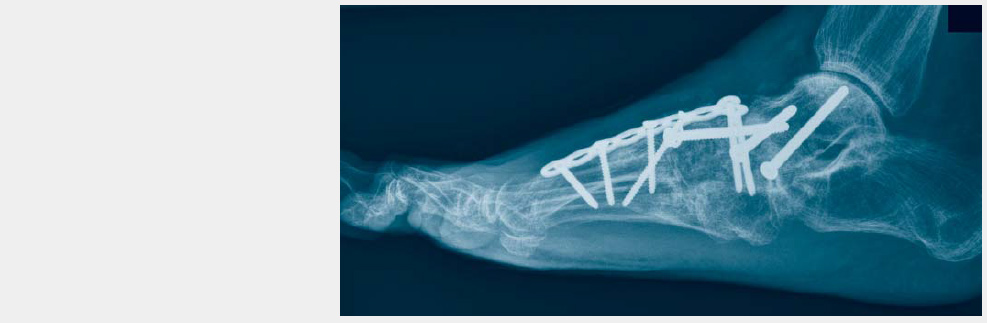

Indications